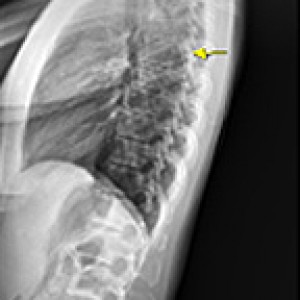

Before & After

해당 사진은 수정없는 실제 치료사진입니다.

환자의 치료결과는 환자의 상태, 치료방법 등에 따라 차이가 발생할 수 있습니다.